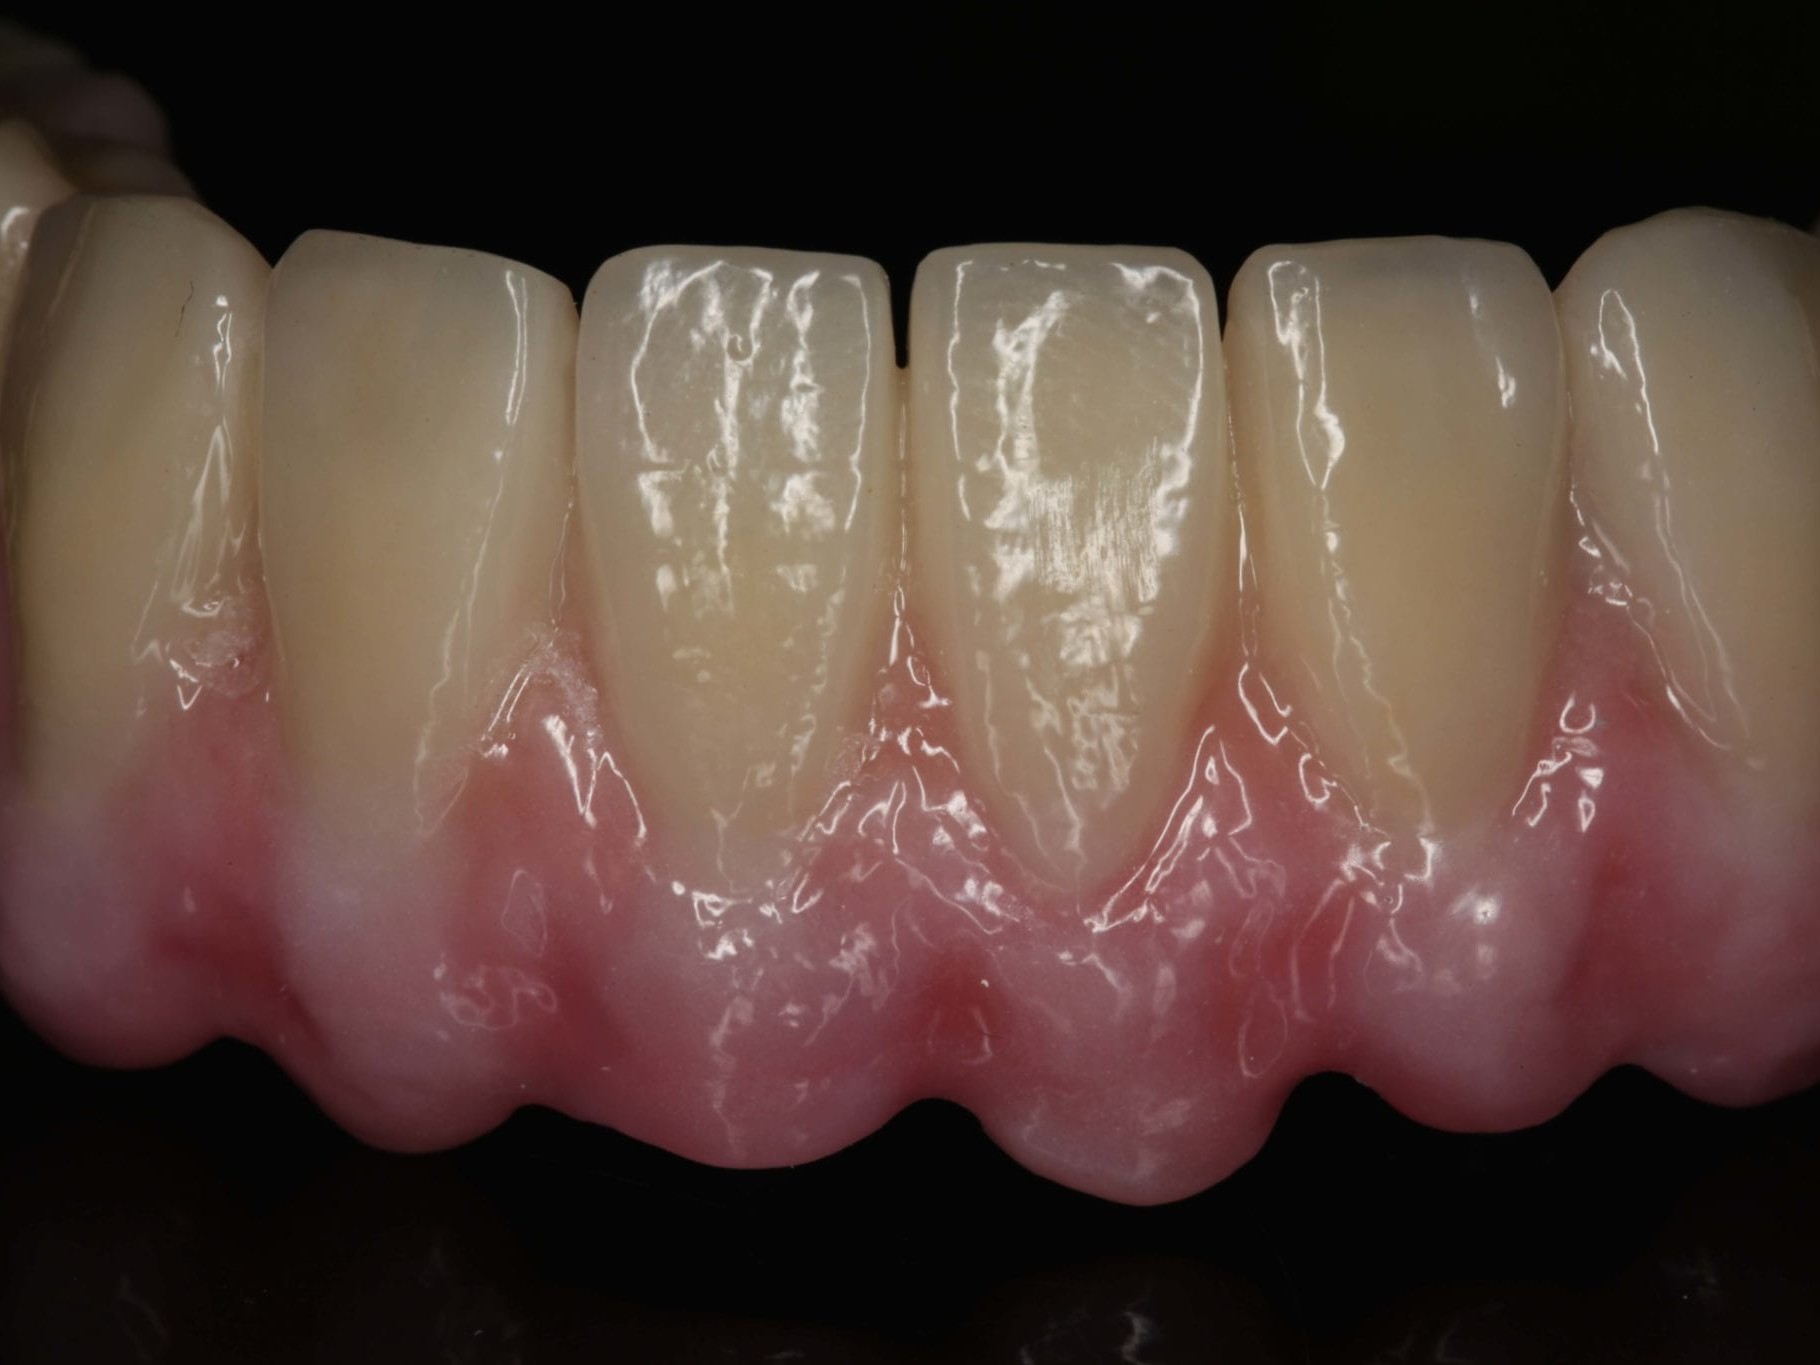

Nach erneuter Überprüfung der implantatprothetischen Sofortversorgung auf sämtliche okklusalen und gelenkspezifischen Parameter erfolgte die Abformung im Ober- und Unterkiefer (Abb. 22). Da die Ankylos Balance-Basis Aufbauten intraoperativ bereits zum Zeitpunkt der Interimsversorgung definitiv eingesetzt wurden, erfolgte die Abformung auf Abutmentniveau mit einem Folienlöffel für präzise Implantatabformung. Um die visuelle Kontrolle über den Abformprozesses zu haben, kam ein transparentes Abformmaterial zur Anwendung. Zur präzisen Übertragung der Mundsituation auf das Modell ist entweder eine zweite Abformung mit einem entsprechenden laborgefertigten Kontrollschlüsssel oder eine direkte intraorale Verblockung der Ankylos Abformpfosten erforderlich¹¹. Bei der letztgenannten Variante werden die direkte Verblockung der Abformpfosten und die präzise Implantatabformung miteinander kombiniert (Abb. 23). Hierfür wird Zahnseide spannungsfrei mehrfach über Kreuz um die Abformpfosten geschlungen. Das hieraus entstehende Gerüst dient als Trägerplattform für das Autopolymerisat, das wir in Pinseltechnik appliziert haben. Um ein zügigeres Arbeiten am Patienten zu gewährleisten, kamen vorgefertigte Stangen (Ø 3 mm) aus rotem Modellierkunststoff zum Einsatz. Dieser Modellierkunststoff zeigt auch bei sehr dünnen Schichtstärken eine minimale Schrumpfung bei hoher Festigkeit sowie Stabilität. Das zeitversetzte Applizieren des Autopolymerisates gewährleistet die Spannungsfreiheit der Verblockung. Das Meistermodell wurde aus Klasse–IV-Superhartgips mit typischer Gingivamaske hergestellt. Bei weitspannigen Suprastrukturen lässt sich die höchste Genauigkeit mit einer verblockten Präzisionsabformung erreichen. Die durch das nach distal ausgedehnte prothetische Polygon bedingte Weitspannigkeit ist das Prinzip des SmartFix-Konzeptes. Nach der Modellherstellung erfolgte die anatomisch korrekte Übertragung der Schädel-Achs-Relation des Oberkiefers in den Artikulator mittels Gesichtsbogen. Zur Montage des Unterkiefers konnte in diesem Fall auf eine klassische Bissnahme verzichtet werden, da das computerdesignte und okklusal verschraubte Langzeitprovisorium während der Einheilphase vom Behandler feinjustiert wurde und somit die Bisshöhe und -lage zur Übertragung perfekt geeignet war. Hierfür wurde das Provisorium entnommen, so dass der Zahntechniker die Artikulation und die damit verbundene Individualisierung der Artikulatorenwerte in der Praxis vornehmen konnte. Im Labor erfolgte die komplette Digitalisierung des Falles. Der gesamte Workflow dieses Patientenfalles beruht auf dem Prinzip des Backward Plannings. Dem Team, bestehend aus einem implantatchirurgischen und einem implantatprothetischen Behandler sowie einem Zahntechniker, ist daran gelegen, sowohl chirurgisch als auch prothetisch vorhersagbare Ergebnisse zu generieren. Bei einer okklusal verschraubten Brücke ist es für den Zahntechniker vor Beginn der Arbeit wichtig, den späteren Austrittspunkt der Schraubenkanäle zu kennen und eine diagnostische Aufstellung in Form und Funktion anzufertigen. Nur so wird gewährleistet, dass das CAD/CAM gefertigte Gerüst die Verblendungen optimal unterstützt und die Schraubenkanäle ideale Durchtrittspunkte bekommen. Durch das im Vorfeld erstellte digitale Sofortprovisorium konnte die ästhetische Ausgangssituation der Patientin sowie die individuellen Okklusionsparameter bis hierhin fehlerfrei übernommen werden. Dieses Sofortprovisorium wurde mittels Alginat in situ abgeformt und nach der Modellherstellung digitalisiert. Zur Steigerung der Präzision wurde darüber hinaus ein klassisches diagnostisches Wax-Up erstellt, das den Verlauf der rot-weißen Ästhetik wiedergab. Diese Datensätze wurden dann mit den Scandaten des Meistermodells in einem CAD Programm gematcht (Abb. 24). Damit standen dem Zahntechniker alle benötigten Informationen zur Erarbeitung eines Designvorschlages für das anatomisch teilreduzierte Brückengerüst aus Zirkondioxid zur Verfügung. Die auf den Zehntelmillimeter genau festzulegende Reduktion des Gerüstes richtet sich nach der Indikation der Verblendung. Wie weiter oben bereits beschrieben, ist die Patientin im Oberkiefer mit einer herausnehmbaren Kunststofftotalprothese versorgt. Aus Sicht des Behandlungsteams war dadurch eine keramische Verblendung des Unterkiefers möglich. Aus Stabilitätsgründen entschied sich das Team für eine Versorgung aus monolithischem Zirkondioxid, das zur Steigerung der Ästhetik von 033 bis 043 vestibulär verblendet wurde (Abb. 25). Die Verwendung von monolithischem Zirkon in Verbindung mit einer keramischen Teilverblendung gewährleistet neben der notwendigen Ästhetik und Stabilität zwei weitere Vorteile. Auf der einen Seite zählt Zirkondioxid in der Zahnheilkunde zu den Materialien mit der höchsten Biokompatibilität und zum anderen werden die auftretenden Kaukräfte gerade in Verbindung mit der Versorgung im Oberkiefer gleichmäßiger auf das Implantat und den Knochen verteilt. Gerade bei implantologischen Oberkiefer- und Unterkieferversorgungen ist dieser „Stoßdämpfer–Effekt“ für den Langzeiterfolg wichtig. Im vorliegenden Fall wurde die okklusal verschraubte Brücke mit einem Sintergerüst versehen und mit einer fünfachsigen Fräsmaschine im Labor aus einem Zirkonblock gefräst. Bevor das Gerüst mit einem speziell entwickelten Langzeitprogramm gesintert wurde, erfolgte die individuelle Einfärbung des Zirkondioxides mit Color Liquids. Die anschließende vestibuläre Verblendung der Zähne und des Zahnfleisches wurde unter Zuhilfenahme der diagnostischen Aufstellung mit Verblendkeramik angefertigt. Hierbei wurde besonderer Wert auf die naturgetreue Nachbildung der Rot-WeißÄsthetik und eine gute Hygienefähigkeit geachtet. Die gefertigte Arbeit wurde mit einem dafür zugelassenen Kleber auf die Ankylos Stegkappen (für Balance Basisaufbau schmal, aus Permador® PDF, Dentsply Implants) verklebt, die zuvor auf dem Meistermodel aufgeschraubt worden waren. In Übereinstimmung mit den als Sheffield-Test¹² bekannten Kriterien der University of Sheffield, GB, ermöglicht dieser Fertigungsprozess in Kombination mit der verblockten Abdrucknahme einen präzisen und somit spannungsfreien Sitz der Brücke – sowohl auf dem Meistermodell als auch im Munde des Patienten (Abb. 26 bis 28). Nach der zahntechnischen Fertigstellung der Unterkieferbrücke wurde diese intraoral inkorporiert (Abb. 29 und 30). Die Ankylos Implantatschrauben wurden mit 25 Ncm angezogen. Wichtig ist, dass stets das Originalequipment des Herstellers oder ein elektronisch kalibrierter Schraubendreher verwendet wird. Die Schraubenkamine wurden mit einem bakteriendichten, formstabilen lichthärtenden Füllungsmaterial verschlossen. Nach 6 Wochen wurde ein abschließendes OPG erstellt (Abb. 31).